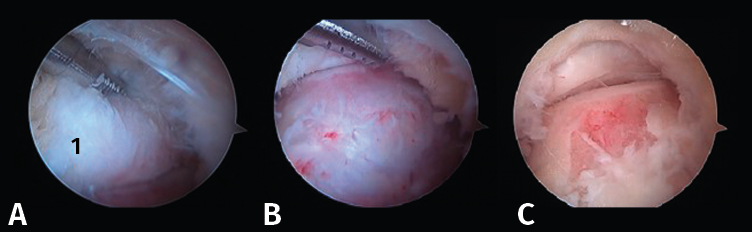

- Tercer paso. El sinoviotomo se gira ahora para que la ventana vuelva a mirar la cara medial del PPA. En este momento, el tendón FHL permanece medial al sinoviotomo y opuesto a su ventana. Podemos así seccionar el retináculo del FHL con el sinoviotomo o mediante una pinza de tipo basket (Figuras 6 A, B y C).

- Cuarto paso: quitar el LACP de la parte inferior del PPA para completar su liberación (Figura 7 A y B).

Figura 6. A y B: liberación del retináculo del flexor hallucis longus (FHL) (1); C: evaluación del interior de la vaina del FHL (2).

Evaluación del tendón flexor hallucis longus

El tendón del FHL se valora sistemáticamente mediante el gancho explorador, pudiendo encontrar tenosinovitis y/o atrapamiento por la presencia de una unión musculotendinosa de implantación baja. A continuación, se introduce el artroscopio en la propia vaina para poder evaluar el resto del recorrido del tendón (Figura 6 C).

Figura 7. A: resección del ligamento astrágalo-calcáneo posterior (LACP) (1) en la parte inferior del proceso posterolateral del astrágalo (PPA); B: PPA (2) después de la resección completa de los ligamentos circundantes.